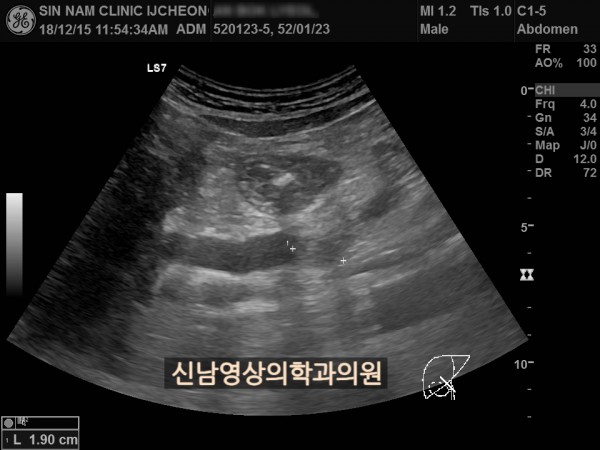

상복부 초음파 적용 사례

본 환자분은 50대 중반의 남성분으로 손가락안이 가렵다는 느낌으로 내원하셨습니다.

담도암과 담관암은 같은 질환을 지칭하는 용어로 간에서 만들어진 담즙이 십이지장으로 이동하는 통로인 담관에 발생하는 악성 종양입니다.

이 암은 간 안에 생기는 간내 담관암과 간 바깥에 생기는 간외 담관암으로 나뉘며, 가장 흔한 증상으로 통증이 없는 황달, 짙은 소변, 옅은 변, 복통, 체중 감소, 소양증 등이 나타날 수 있습니다.